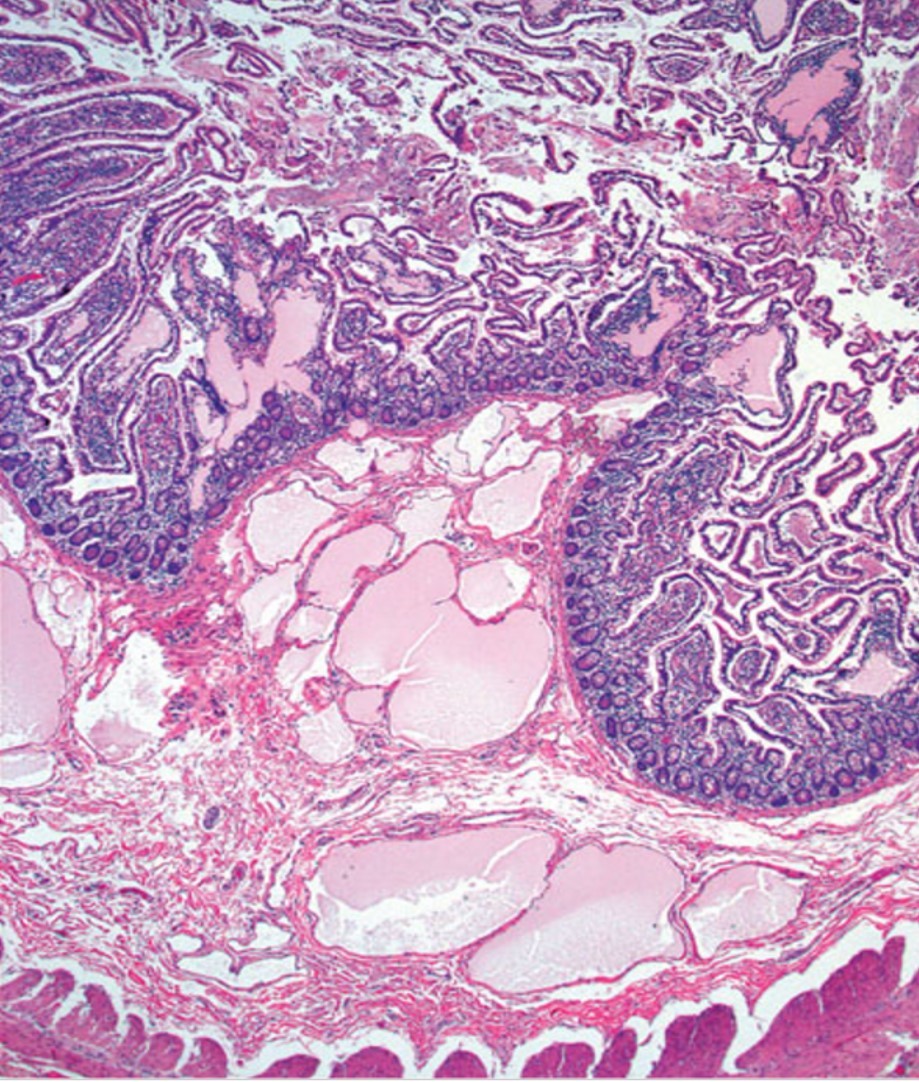

Lymphangioma of the small intestine and mesentery